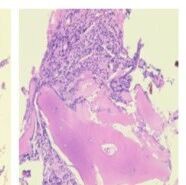

腹水细胞学三检纠偏,助诊潜伏间皮瘤:一例胸腹水细胞形态学在确诊恶性间皮瘤中的关键作用